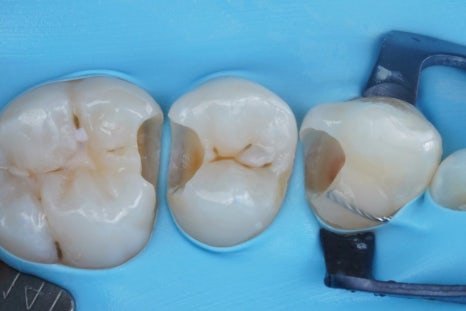

접착 치의학에 기반한

최소침습 치의학,

<레진 빌드업>으로

당일에 끝낼 수도 있습니다.

그리고 이렇게 하기 위해서는

러버댐이라는 재료를 잘 써야 해요.

러버댐을 잘 쓰는 것이

가장 중요한 첫단계입니다.

러버댐이라는 재료는

그냥 썼다고해서 다 된 게 아니라

그 목적을 이루기 위해 필요한 여러 원칙들을

하나하나 지켜야만

원하는 결과를 얻을 수 있겠죠.